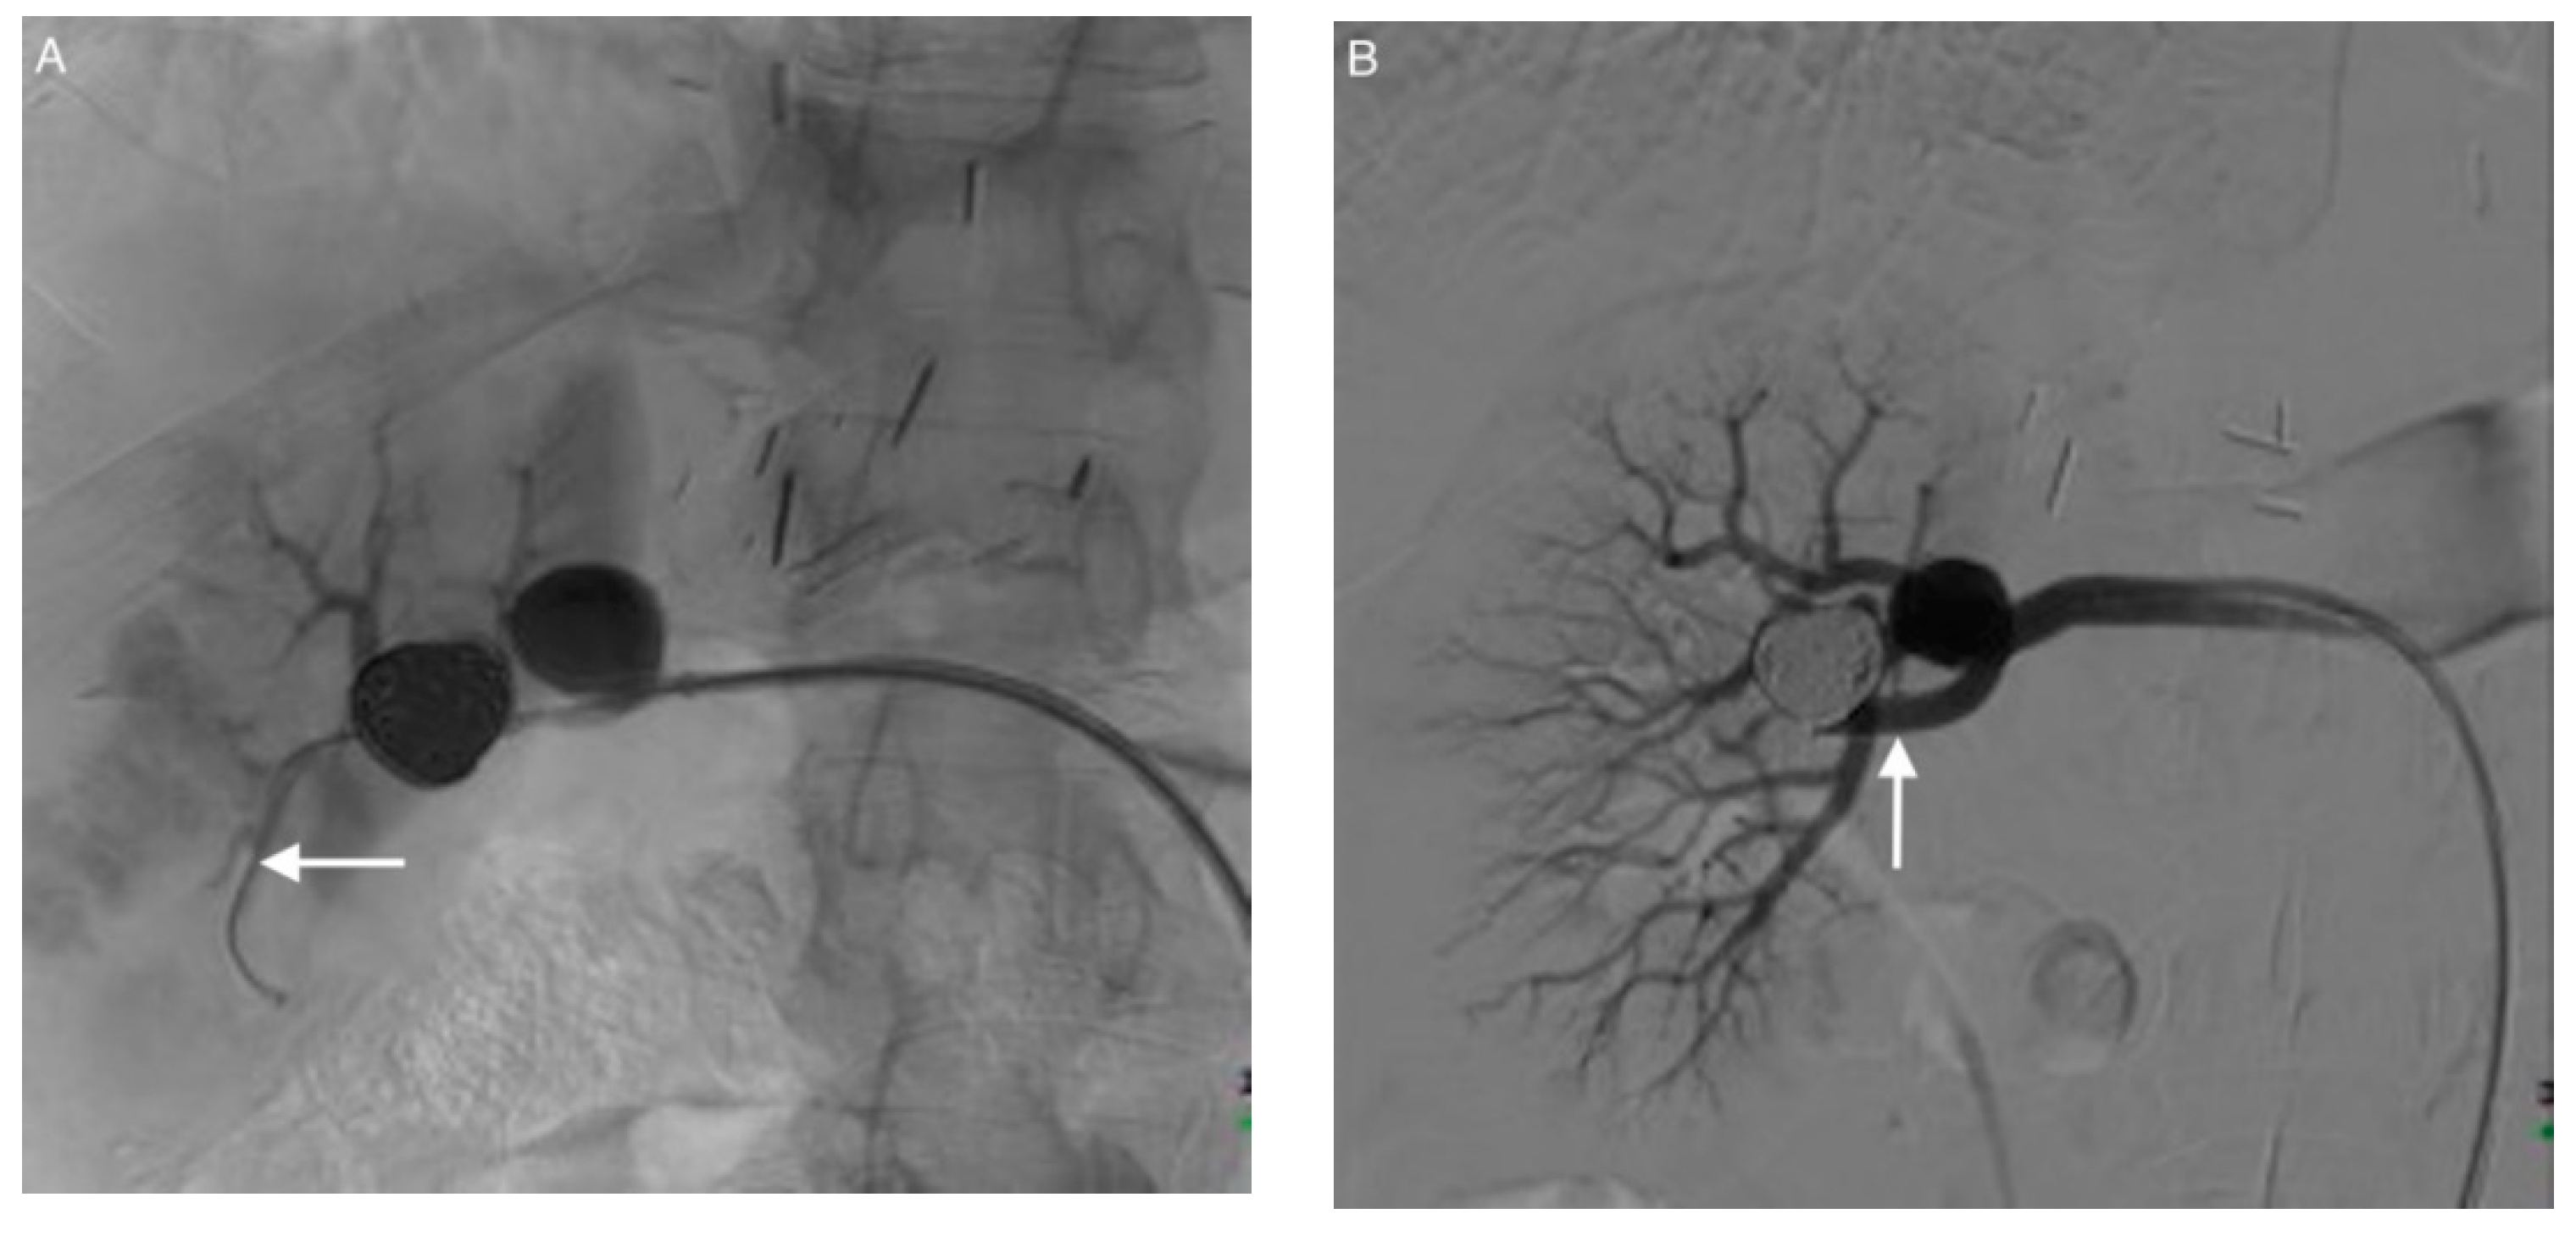

2.2. Endovascular Procedure

3.3. Coil Embolization and Outcomes

3.4. Complications